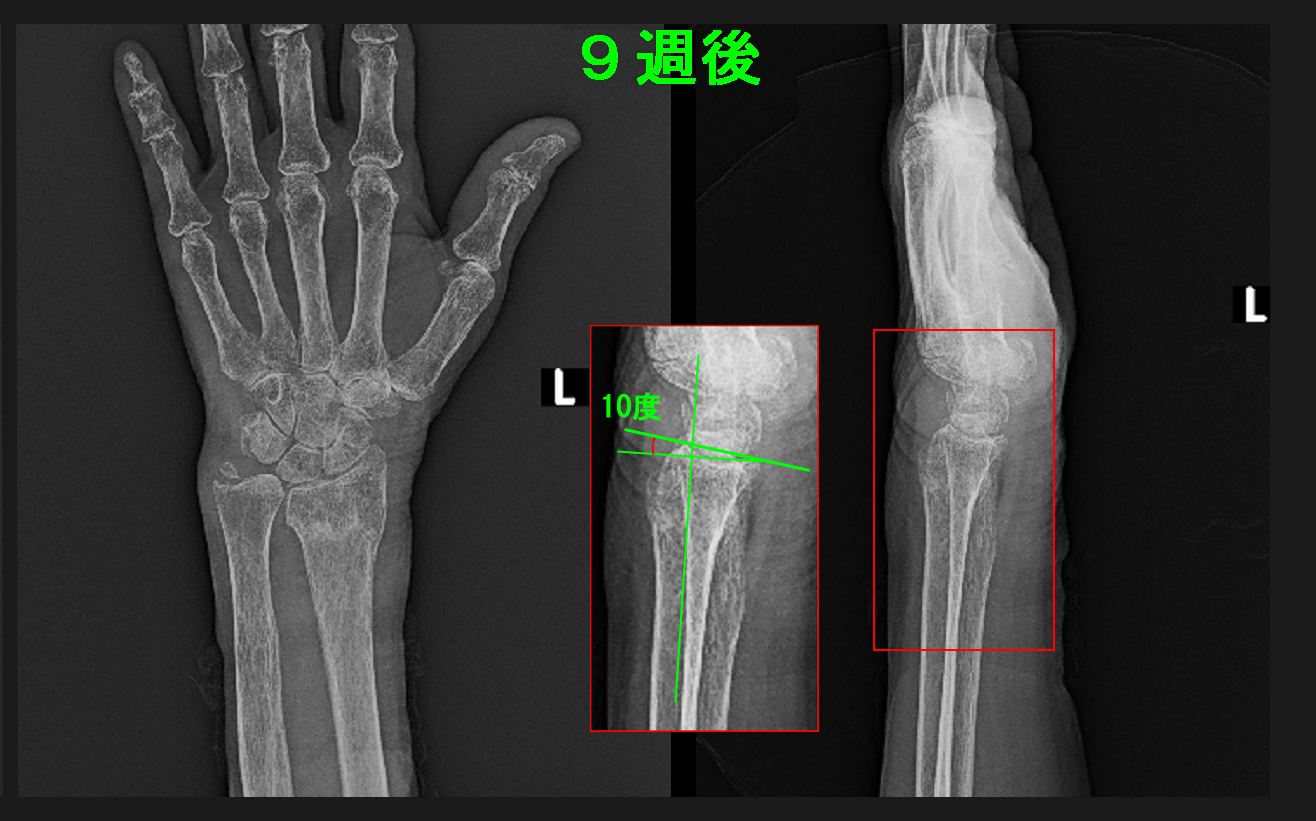

5週で針金とギプスを除去し、リハビリを開始しました。この92才の女性は几帳面な方で、7週以後の受診時には毎回自分で和服を着て受診されていました。9週後には日常生活に支障がなくなり治癒となりました。

9週後Xp.jpg

最終レントゲンで手関節面の傾斜は手のひら側に10度の傾斜となっていて、良好な治癒状態です。